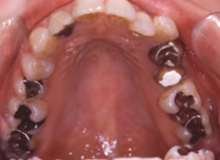

(治療前:写真左)

態癖の影響が強く奥歯が舌側に傾斜し、八重歯になっています。